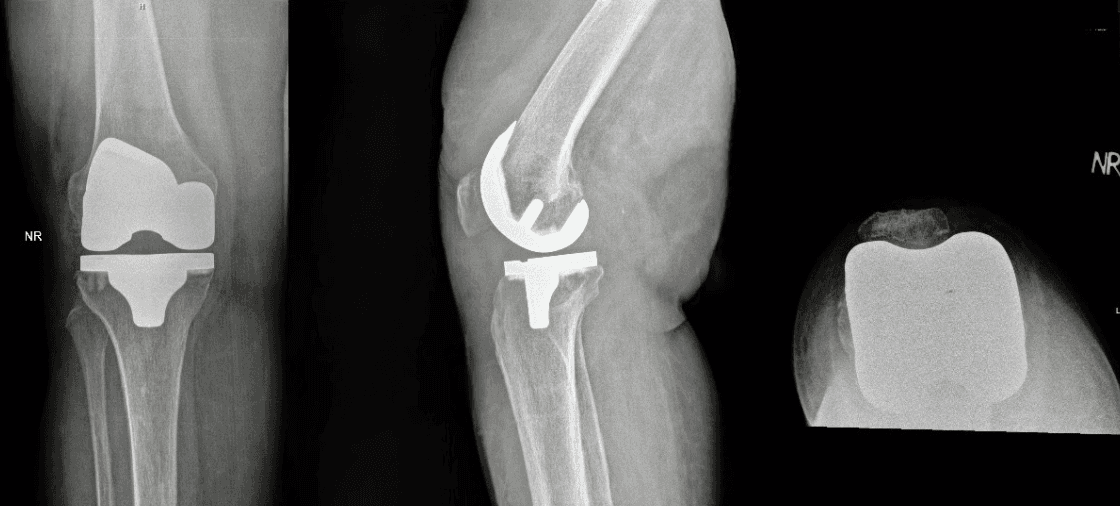

The worn-out bone and cartilage surfaces are carefully removed and replaced with high-quality metal and plastic implants that mimic the natural movement of the knee.